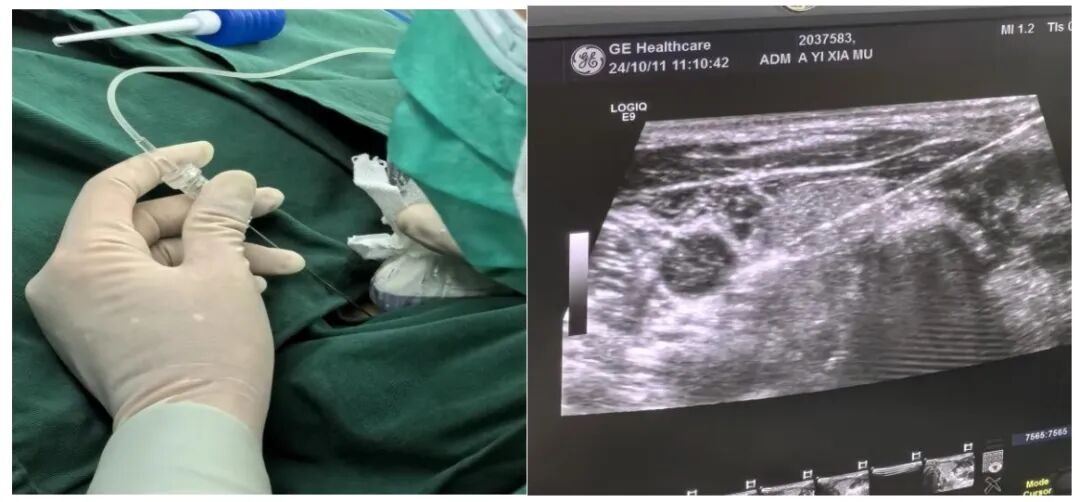

目前超声引导下的甲状旁腺病变消融术仅需一根细针便可达到外科手术效果,缓解患者病痛,具有精准、微创、效率高及安全性相对较高等特点,术后患者即刻可以下床活动,骨痛、皮肤瘙痒症状明显缓解。这种新型治疗方式,可以让更多的终末期肾衰竭患者获益。

术中细针操作及B超引导视野